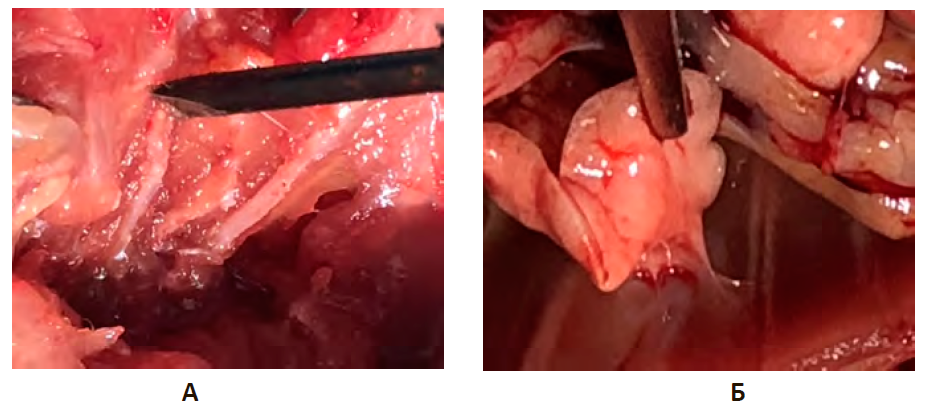

К окончанию эксперимента (30-е сут.) в группе PRPт тотальное заращение плевральной полости наблюдалось в 13,3% (4 случая). На рис. 4Б представлена наиболее типичная ситуация, характеризующаяся формированием плоскостной интимной спайки в месте перелома при биостимуляции адгезиогенеза плазмой, обогащенной тромбоцитами. Протяженность спайки – 10 мм, ширина 4 мм, толщина до 1 мм, общая площадь органной спайки составила 40 мм2, отмечалось оскуднение васкуляризации по сравнению с предыдущим сроком.

Рисунок 4 – Плевральная полость на 30-е сутки экспериментальной травмы грудной клетки

Примечание: А. Группа негативного контроля. Наличие консолидации переломов ребер, отсутствие внутриплевральных спаек. Б. Опытная группа. Введение плазмы, обогащенной тромбоцитами (PRPт). Формирование плоскостных спаек.